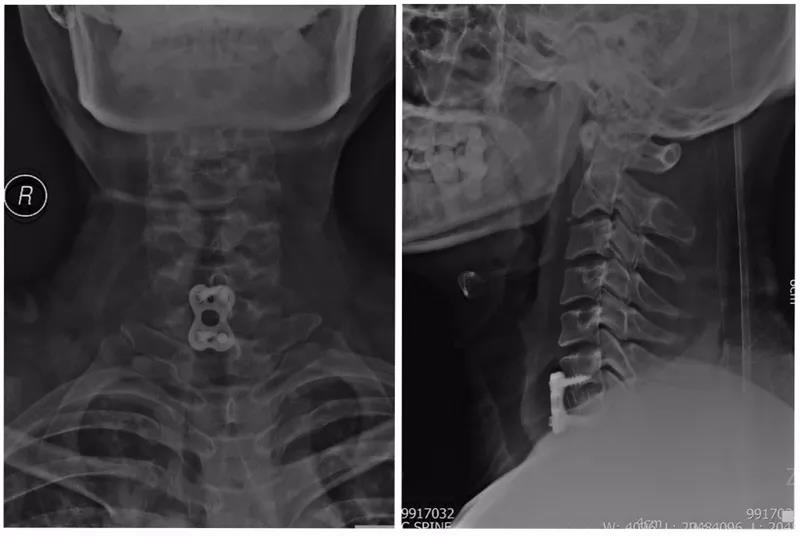

术前X线正侧位片

术前CT

术前MRI